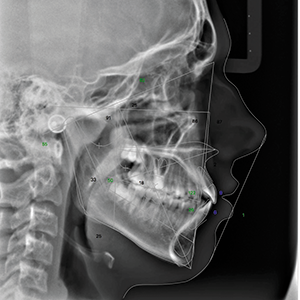

Panoramic analysis showed no pathology and third molars were developing normally (Fig. 2). When this case was started, CBCTs weren’t routinely being taken on all patients. That has changed because of Ultra Low Dose™ technology, which has been developed by Planmeca. Currently, the author is using the ProMax® 3D Mid X-ray Unit, which allows for an Ultra Low Dose CBCT full field of view (FFOV) to be taken with lower radiation (<15 microsieverts) than traditional 2D digital radiography.

Fig. 2